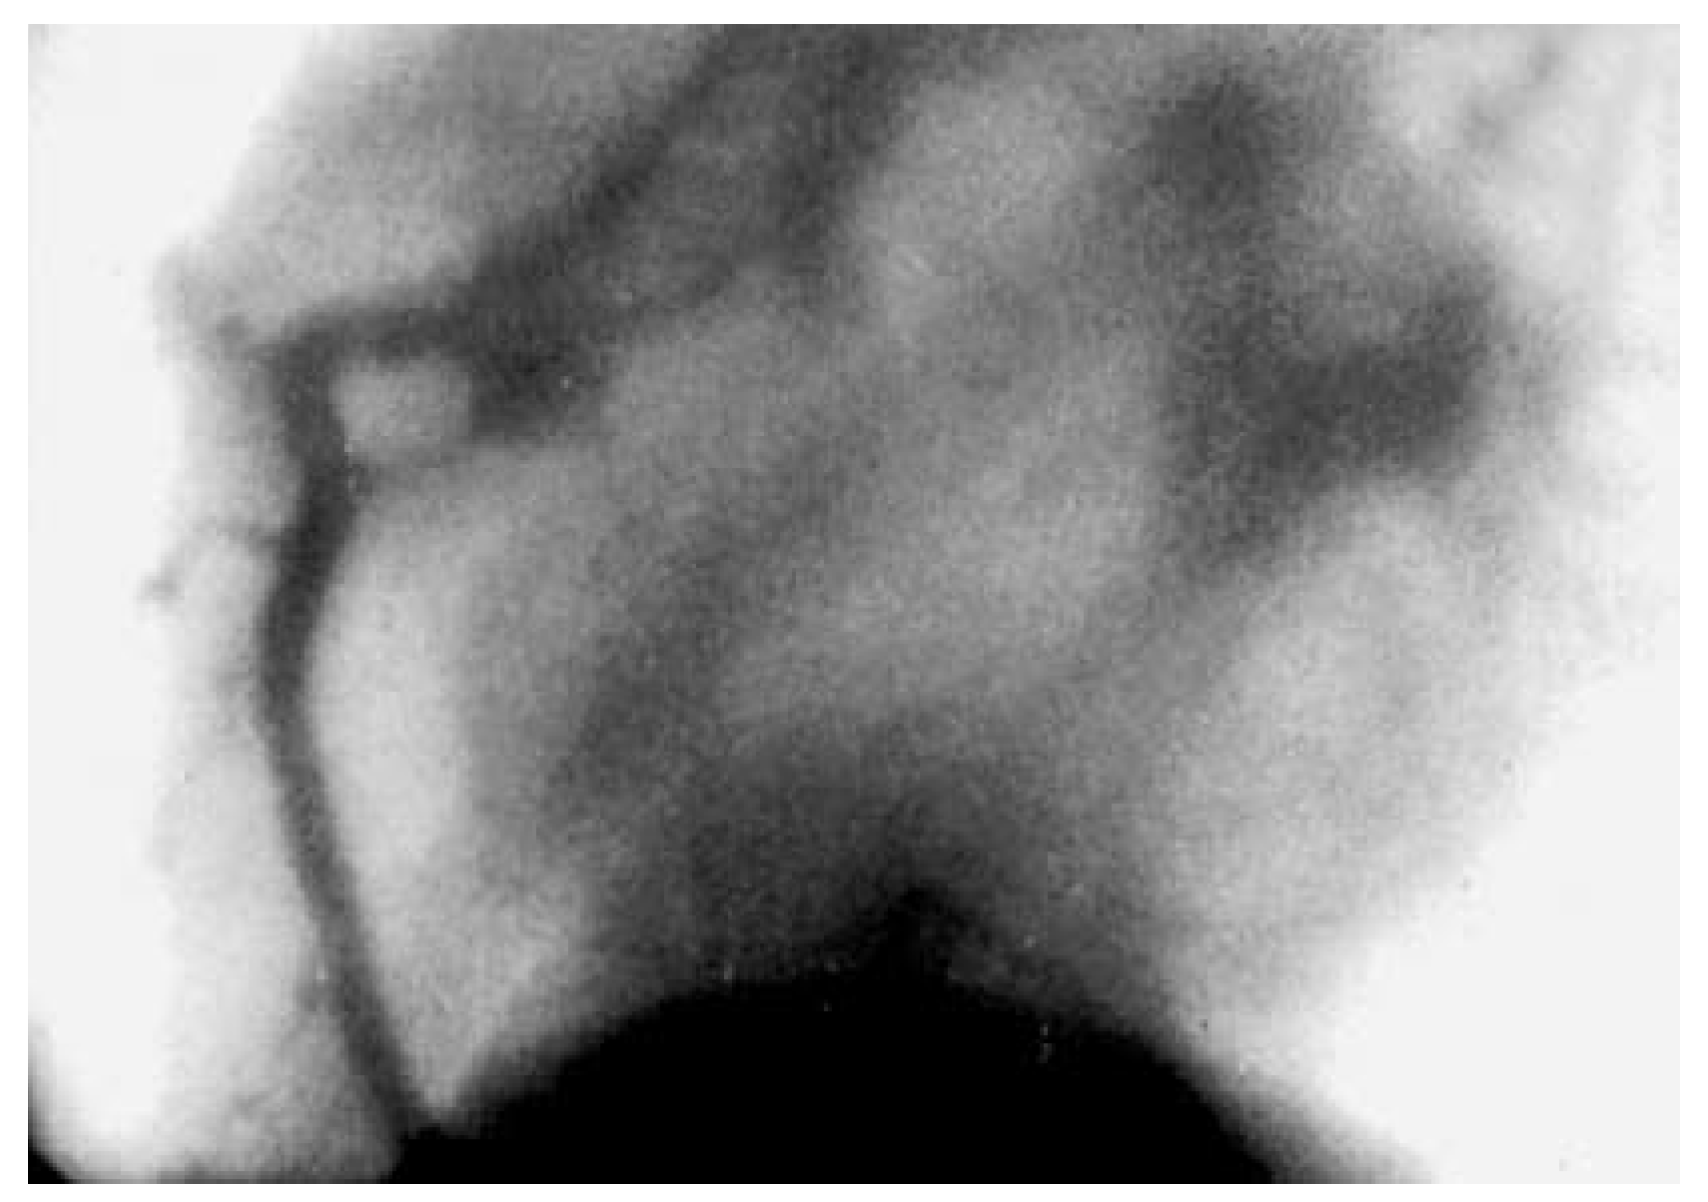

Figure 3. Top: CT done for screening for coronary artery disease in a 54-year-old asymptomatic Hungarian business man who was subsequently urgently flown to Switzerland for immediate angiography and therapy. Bottom: Angiography revealed only minor wall irregularities and uncovered the CT as blatantly false positive.

Simple calcium scoring imparts 1–2 mSv on the patient [31]. However, calcium scoring has been abandoned because calcium is invariably present in people older than 50 years and it is difficult to create an algorithm that tells significant (relevant for lumen) from insignificant (eg, adventitial) calcifications. The recent report showing a good correlation of coronary calcification detected by CT with all-cause mortality appears rather trivial, irrespective of the adjustment for age [32]. Calcification (not unlike grey hair) is a surrogate of biological (not necessary chronological) aging and therefore impending death. For a multislice coronary angiography, at least 10 mSv have to be invested, with the current 64-slice machines the exposure approaches 20 mSv. This is bound to increase when moving to 256-slice equipment although the use of a dual source may curb the radiation exposure somewhat. Conventional coronary angiography (monoplane or biplane) ranges in the realm of 5 mSv [33]. This allows adding therapy (percutaneous coronary intervention) and still staying below the radiation dose of CT angiography. For comparison, men are exposed to an annual dose of about 2 mSv from natural sources and radiation workers are monitored not to exceed a dose of 15 mSv per year [31]. Combining CT angiography with a functional test such as SPECT or PET doubles the dose to 30–40 mSv. Applying this combined technique (Figure 4) raises ethical questions considering the fact that radiation-free alternatives are available for the functional part (MR and stress or exercise echocardiography) and the anatomical information can be collected with 1/10th of the dose.

Figure 4. Integrated 64-slice CT-angiography and SPECT-imaging. The left picture indicated the myocardial perfusion deficit of the diseased (stop of flow) diagonal and marginal branches (arrows) which provides additional information to the purely anatomical picture at the right which shows that the proximal stents are patent. (With courtesy: Syntermed Software and C.A. Santana, MD, Emory University, Atlanta, GA, USA.).